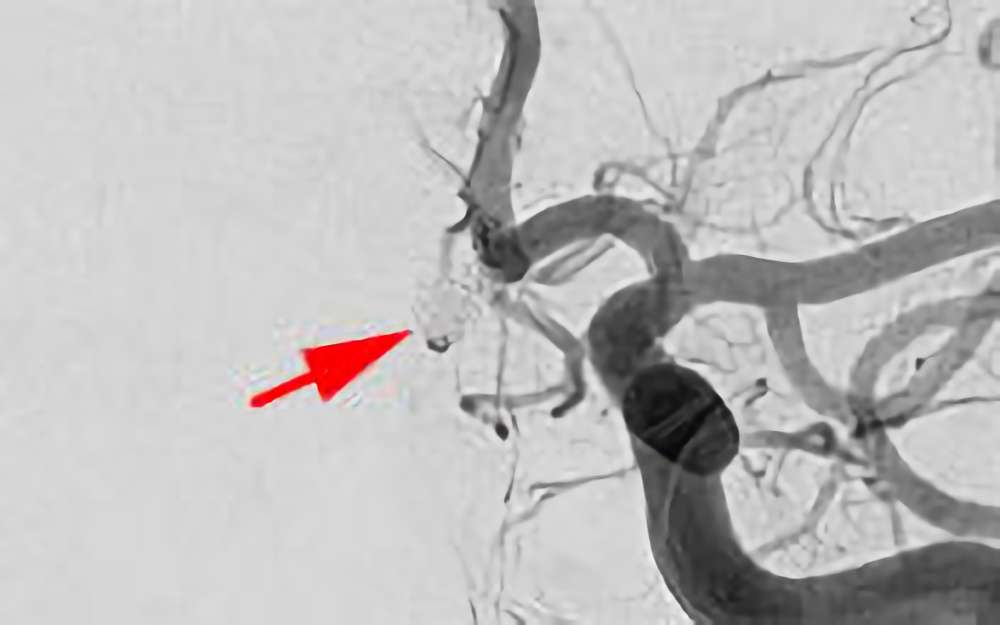

No.1600 手術前